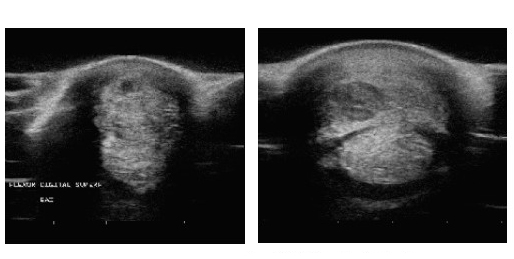

CAMPOS, MJ1. AGÜERA E.I. REQUENA F. 세포생물학, 생리학, 면역학과, 코르도바 대학교 연구박사 ” 448KHz 수용성/저항성 단극성 고주파를 말의 등간 힘줄 병리학에 사용”.

2주간 8회 세션 치료 / 부상

치료 전

치료 후